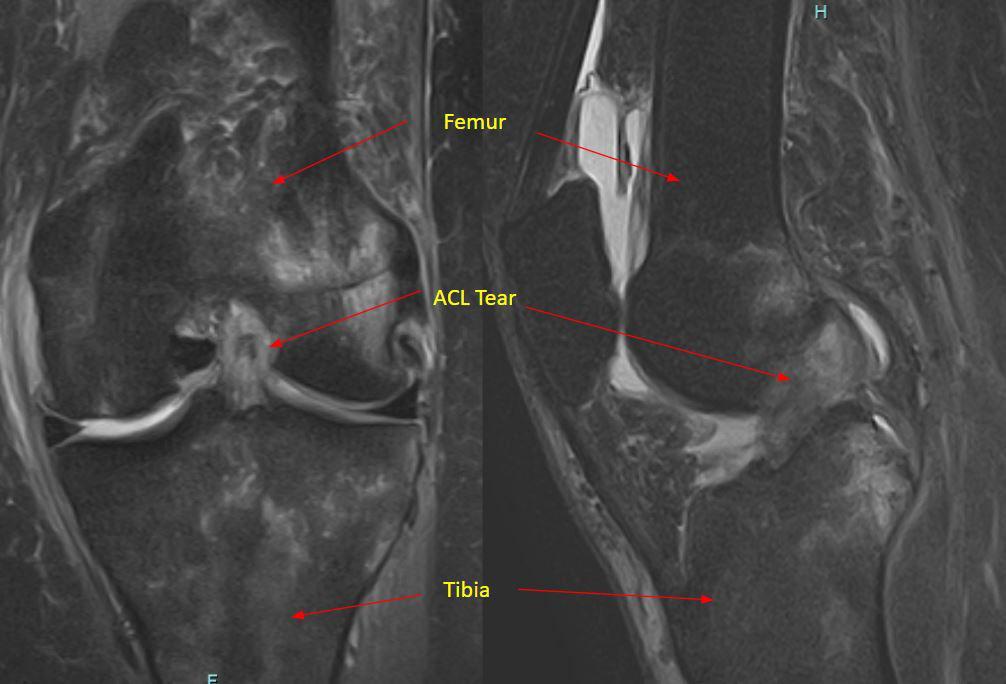

Dr. Pancio studied my daughters MRI before he came in and talked to us. He examined her knee and told us that her exam confirmed what he had found on the MRI which was missed by the radiologist. He prescribed the appropriate physical therapy and my daughter is on her way to making a full recovery without surgery! If she would have needed surgery, we have full confidence that Dr. Pancio would be great! He is very observant and knowledgeable. He explained everything that is going on with her knee also why and when it would hurt in different situations.